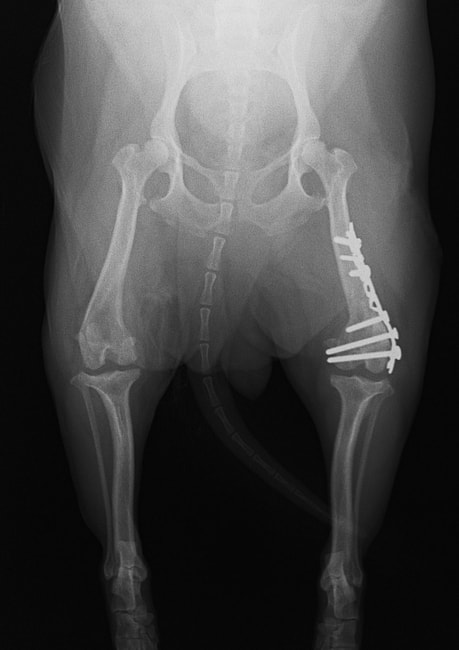

■ 症例24 キャバリア 7か月

左右膝蓋骨内方脱臼(左:グレードⅣ 右:グレードⅢ)

以前から左右後肢の跛行が認められ、整形外科学的検査・レントゲン検査により左右の膝蓋骨脱臼が認められた。症状が重度である左膝の膝蓋骨脱臼整復術を行った。外科手技は縫工筋及び内側広筋の解放、脛骨粗面の外側転位、滑車ブロック形造溝術、内外側関節方の縫縮を実施した。術後一か月時点で、左の膝蓋骨は安定しており経過は良好である。

本症例は成長期における重度の膝蓋骨脱臼であり、術後の再発の可能性もあるため、経過をしっかりと観察していく必要がある。また、今回手術を実施していない右膝に関しても経過を観察し、手術を検討していくこととする。